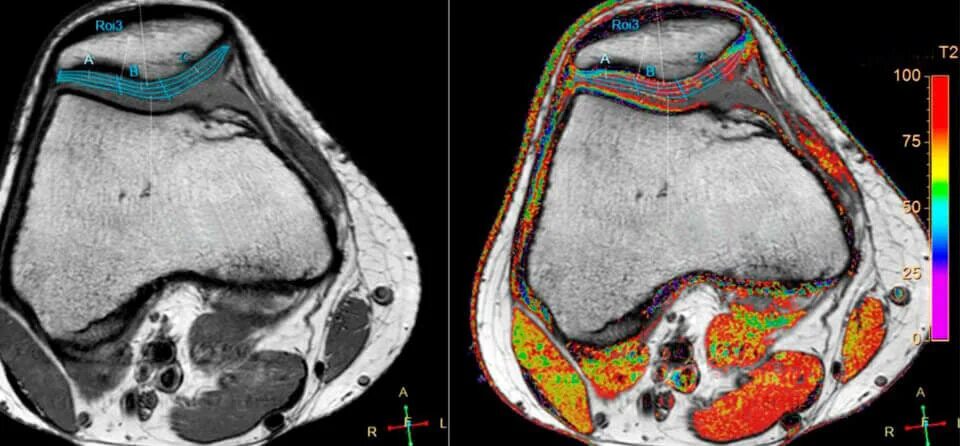

Повреждение хряща по outerbridge